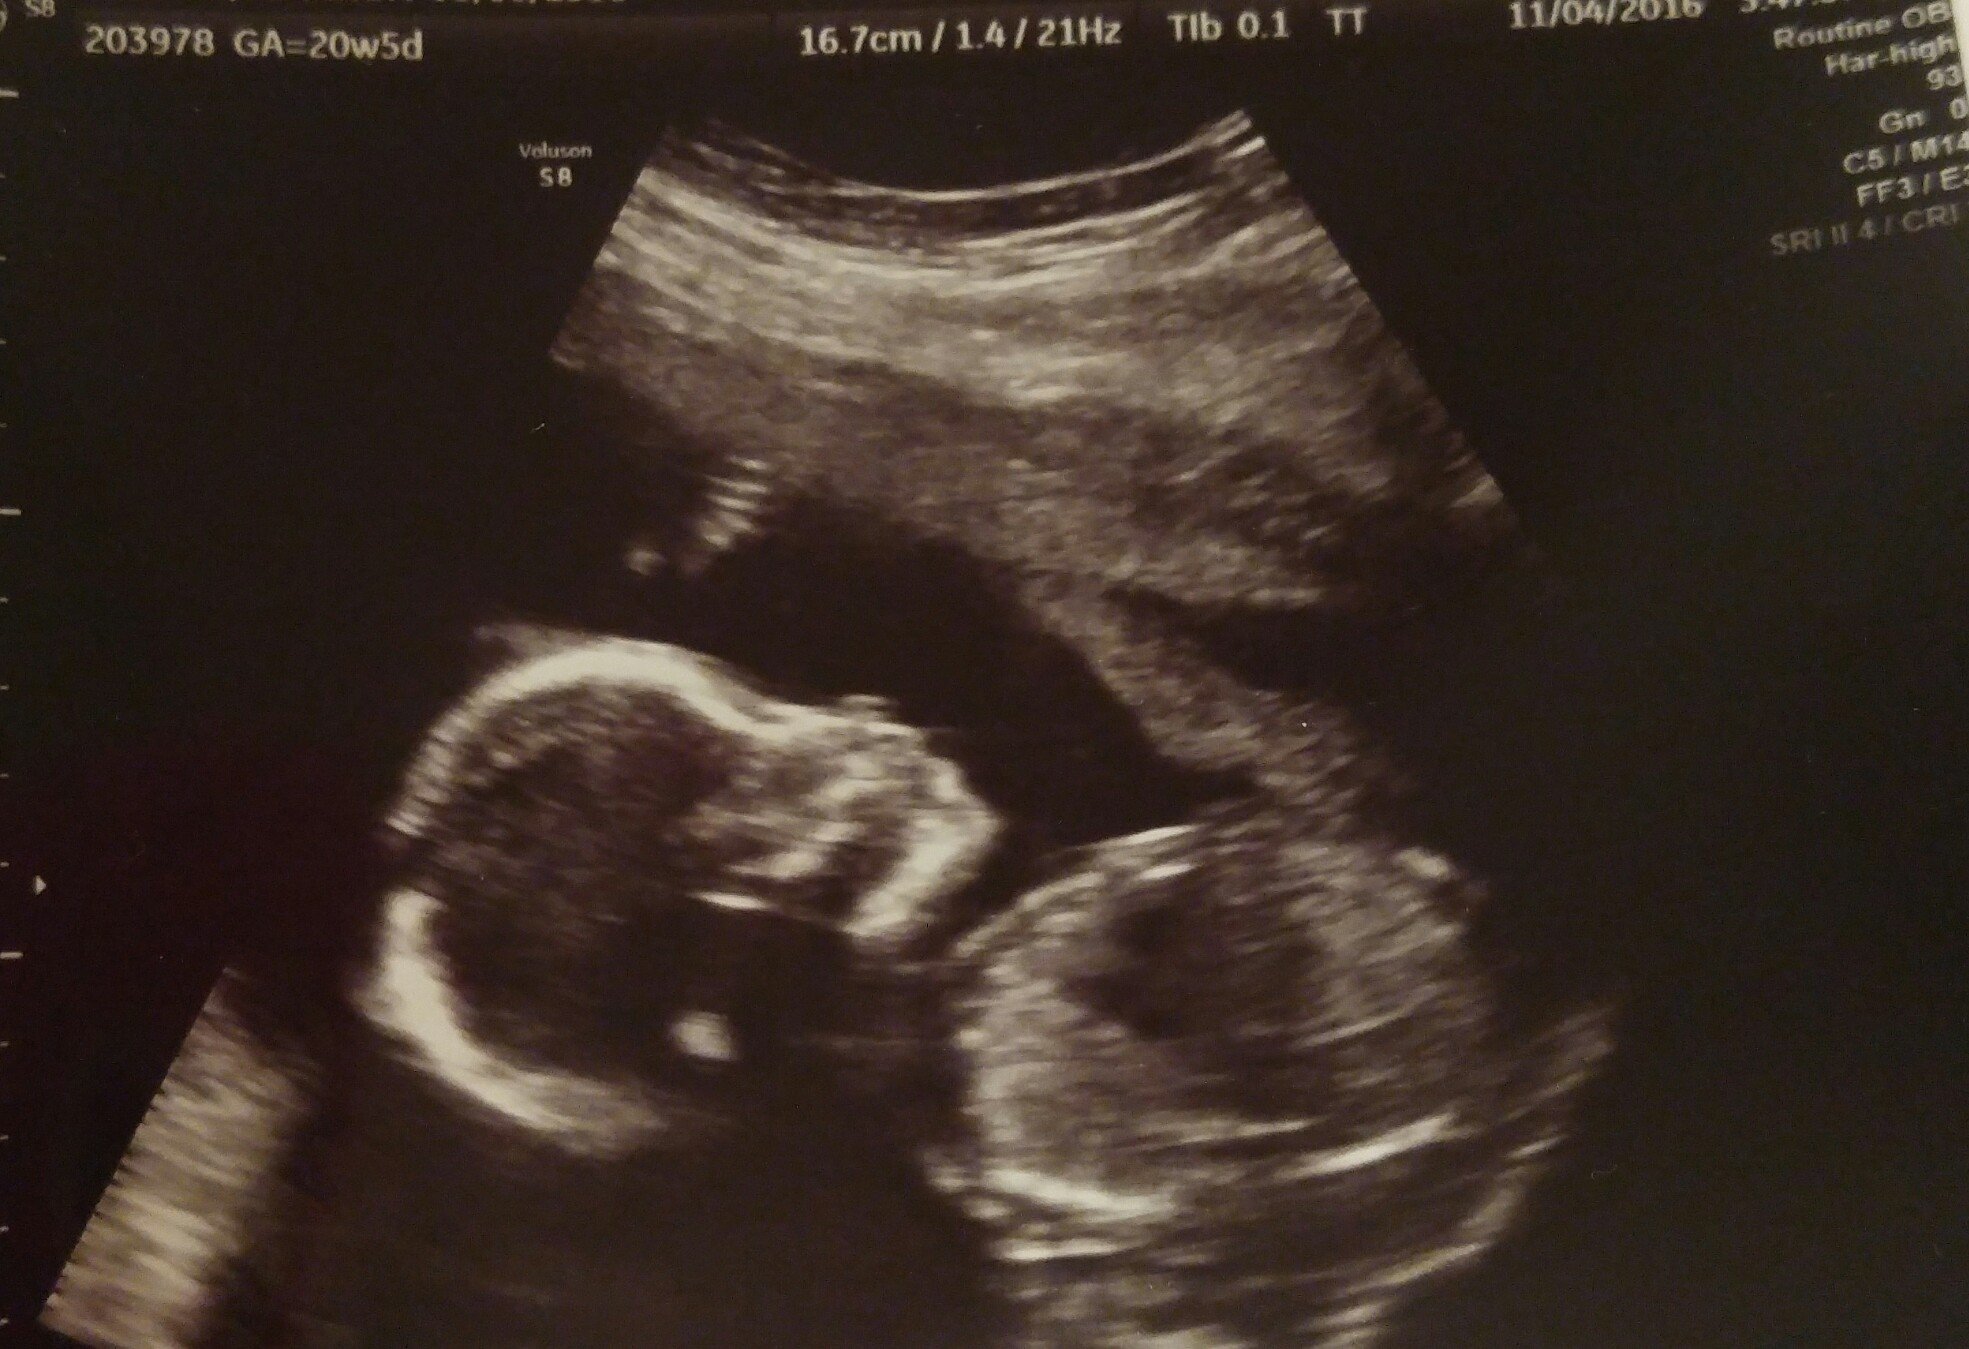

Baby girl at 20 weeks. We got an adorable video of her sucking her thumb but I can't figure out how to post it here. I swear she looks like her dad and has his feet.

Baby girl at 20 weeks. We got an adorable video of her sucking her thumb but I can't figure out how to post it here. I swear she looks like her dad and has his feet.Me 28 DH 28 Married 2012

TTC #1 since March 2015

Metformin + Femara + Gonal F + Trigger = BFP 6/24/16

EDD 3/3/17

Found out it's a girl! 9/23/16